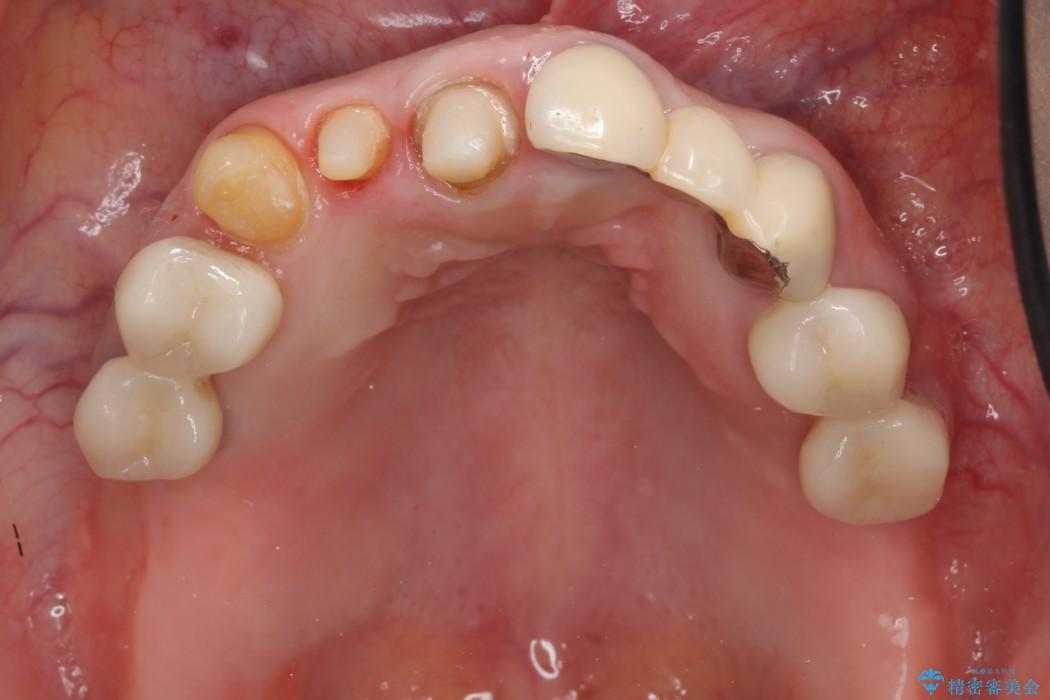

前歯のかぶせ物に関しましては、内面が金属で覆われているため歯茎にその色が透けて見えるという審美的な問題と、かぶせ物と歯の境界が不適合であるという問題がありました。

犬歯の虫歯につきましては、何度も詰め物治療が繰り返されている痕跡があり今回虫歯を取りきるにあたり歯の強度に不安が残るため前歯と同時にかぶせ物の治療をしていくことを計画しました。

今回の症例では金属の色が透けていることを気にされていたので、土台から金属を除去し、金属を使用していないオールセラミックのかぶせ物を使用することとしました。